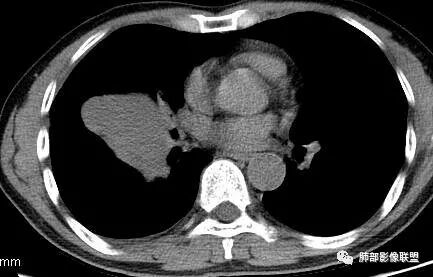

南边:深分叶、大肿块

南边:主体在下叶前基底段

南边:边缘膨隆

南边:中叶、下叶背段支气管推移

南边:中叶支气管腔内似有粘液栓,外侧段有炎性病变

南边:有老师问为啥考虑中叶支气管受压?不是支气管来源的?

1、主体病灶在下叶

2、支气管腔还在,有移位